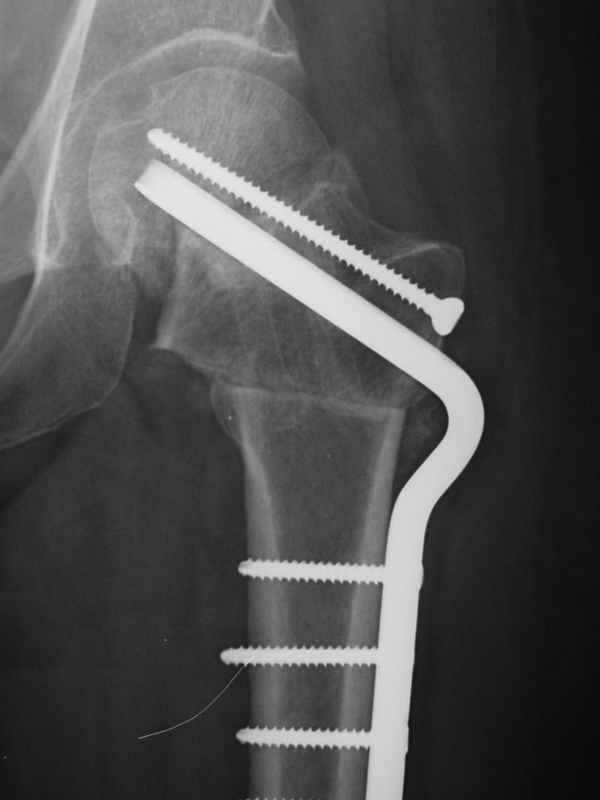

При явно выраженном варусе и флексионных состояниях после сросшихся переломов шейки бедра у молодых рекомендуется реконструктивная операция по исправлению варуса для предотвращения раннего деформирующего артроза, приводящего в результате переднего импинжмента, как показано на снимке.

Межвертельная вальгусная остеотомия представляет наименьший риск среди всех реконструктивных операции в проксимальной части бедра, создавая наилучшие биомеханические условия (увеличивается сила абдукторов, увеличивается сила суставной реакции, уменьшение рычага моментов абдукторов и уменьшение скольжения) и при меньшем риске повреждения кровоснабжения головки, где обычно в 90% случаях достигается отличный результат при применении метода для лечения ложных суставов шейки бедра.

По моему, 120 градусная угловая пластина blade plate решит все проблемы, только необходим предварительный расчет угла остеотомии, и во время фиксации пластины не забыть латерализацию бедра, иначе ось конечности от варуса перейдёт в нежелательный вальгус.

Для предупреждения вальгуса клинок пластины берется на 10-12 мм длиннее чем предварительный туннель на головке, тогда во время

фиксации за бедро пластина автоматически приблизит бедро и происходит латерализация бедра. Если между клинком и латеральным кортексом бедра положить частицу кости от остеотомии тогда образуется дополнительная компрессия на фокусе несращения.

the best option is valgus osteotomy with DHS and also additional canceelous screw fixation. the idea is to convert vertical shear foeces to horriszontal

compressive force

Межвертельная остеотомия менее травматична из-за внесуставного вмещательства, возможны раннее д вижение в суставе сразу после операции, и нагрузка после 3-4 недели, что дает хорошие функциональные

результаты, чем долгое ожидания при спонгиозной фиксации без исправления деформации.

Конечно, нужен определенный опыт по расчету при планировании операции. Я уверен что для коллег технические вопросы операции AO Blade plate

technique не являются сложными, и без боязни на раскол головки или дополнительные повреждения можно исполнить операцию (кстати Др. Волошин из Москвы продемонстрировал прекрасные результаты